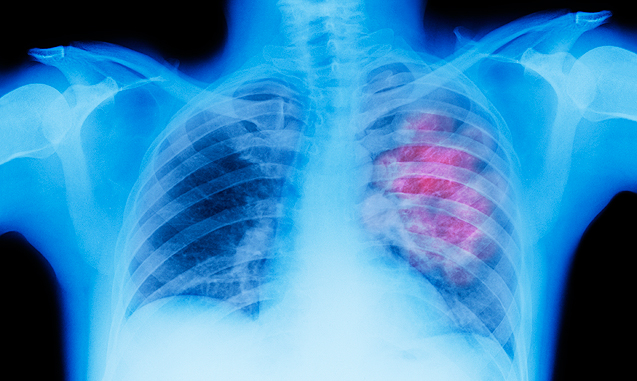

Ο καρκίνος του πνεύμονα αποτελεί σήμερα διαδεδομένη νόσο. Είναι ο δεύτερος σε συχνότητα καρκίνος σε άνδρες και γυναίκες και ο πρώτος σε θνητότητα. Σχετίζεται αποδεδειγμένα στο σύνολό του σχεδόν (πλην ενός μόνο τύπου) με το κάπνισμα (ενεργό και παθητικό), έχοντας άμεση σχέση με τον αριθμό των τσιγάρων που καταναλώνονται καθημερινά. Αυτός είναι ο λόγος που τις τελευταίες δεκαετίες η συχνότητά του αυξήθηκε στις γυναίκες οι οποίες «απελευθερωμένες» πλέον άρχισαν να καπνίζουν. Σε μικρότερο βαθμό παίζουν ρόλο, περιβαλλοντικοί παράγοντες, συνοδά νοσήματα, η κληρονομικότητα, η ηλικία κ.α.